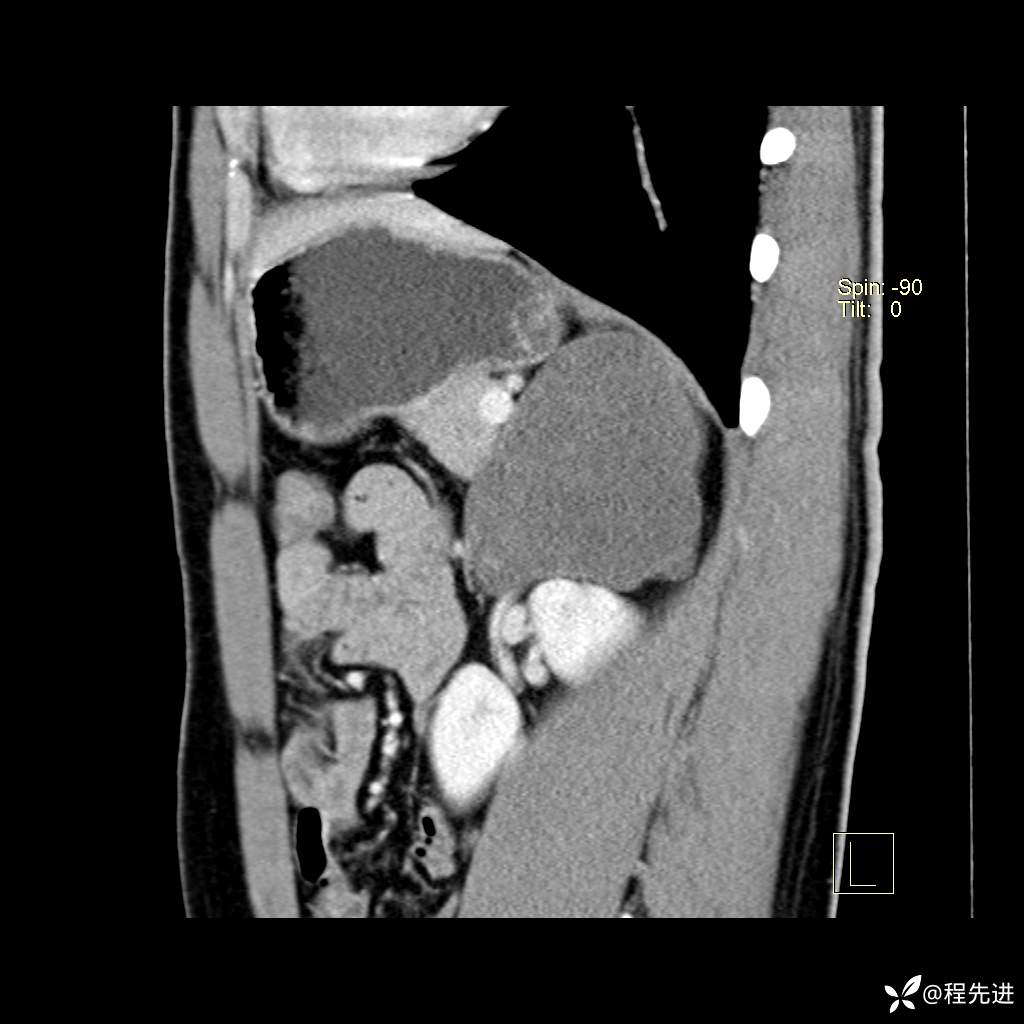

矢状位重建: